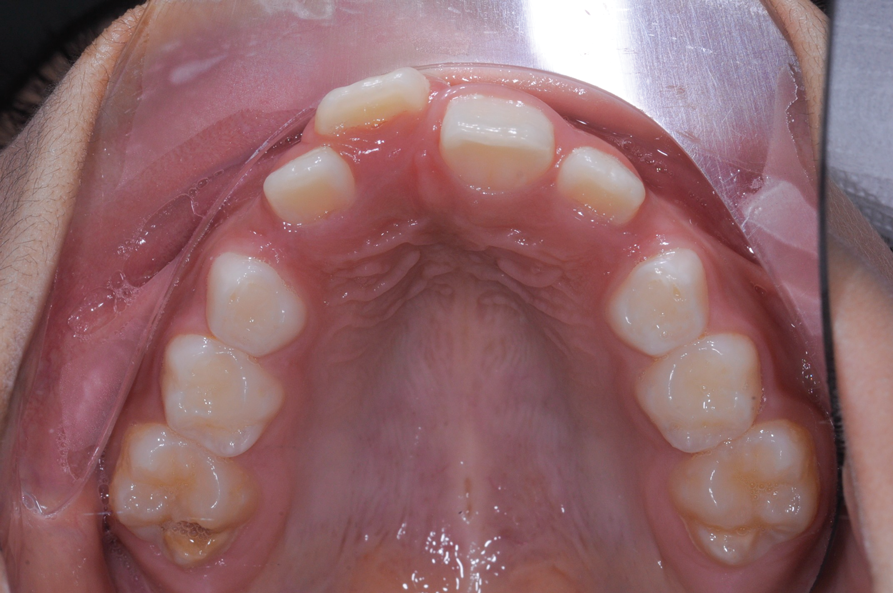

The maxillary right permanent centralincisor had a delayed eruption of 1½ years compared to its homologous incisor, and it was anteriorly displaced due to insufficient space in the premaxilla. Removal of the maxillary deciduous canines was indicated to unravel the crowding. An apically positioned flap of the impacted right central incisor was made to facilitate its eruption (Figure 5 and Figure 6). The case was worked up to plan an active phase l treatment, consisting of palatal expansion and the use of sectional fixed appliances in the upper arch. A transverse deficiency without posterior crossbite was identified, and therefore palatal expansion with a bonded expander was planned to widen the premaxilla (Figure 7 and Figure 8). A two-by-four fixed appliance system (brackets in the four maxillary anterior teeth and bands on the maxillary first molars) was used to align the maxillary teeth. The gingival margin of the retained maxillary right central incisor was slightly more apical than the left one, which erupted as expected (Figure 9 and Figure 10). Figure 11 shows a panoramic radiograph taken after completion of phase 1 treatment.

Fig 9. Clinical situation after completion of phase 1 treatment that allowed the impacted maxillary right central incisor to be properly positioned in the arch, frontal view (Fig 9) and occlusal view (Fig 10).

Fig 10. Clinical situation after completion of phase 1 treatment that allowed the impacted maxillary right central incisor to be properly positioned in the arch, frontal view (Fig 9) and occlusal view (Fig 10).

Figure 10